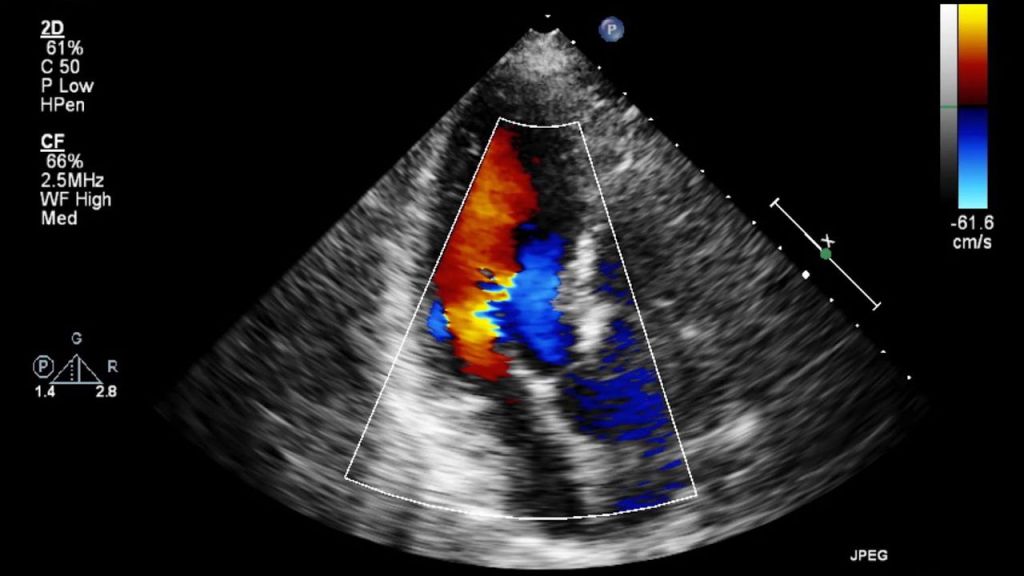

The screen pulses with inscrutable signals,

valves undulating like petals, caught in the winds

of blood. Fingers on a keyboard induce

sudden colors to fly across the screen, like

tropical birds. Crimson, indigo.